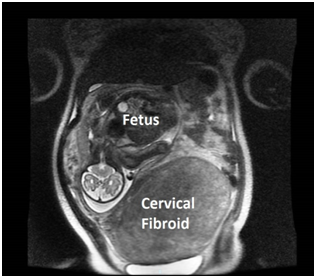

A 31-year old primigravida booked early in her pregnancy at 13 weeks gestation. At her booking visit with her private obstetrician, the dating ultrasound showed that she had a large cervical fibroid 11.9 x7.8cm in size. Subsequently, the woman transferred her care and booked at our tertiary institution at 16 weeks gestation. At 18 weeks gestation, the cervical fibroid had increased to 15.0 x14.4 x8.9cm in size. Her fetal anomaly scan at 21 weeks gestation was otherwise normal, but the fibroid increased in size gradually during her antenatal visits. At 33 weeks gestation, Magnetic Resonance Imaging (MRI) pelvis was performed and ruled out sarcomatous changes in the fibroid; however the cervical fibroid was then 23.0 x14.2 x 23.2cm (Figure 1). Serial ultrasound scans indicated that the fetus’ growth was appropriate for gestation but the fetus remained in breech presentation most of her pregnancy. The woman remained asymptomatic except for one episode of non-specific abdominal pain in her second trimester, which was conservatively managed with oral analgesia.

Figure 1 MRI image of the fetus and the large cervical fibroid at 33 weeks gestation.